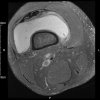

(2016) Patient (male) aged 44 attends physical therapy department with right knee pain. He gives a 5 year history of knee pain. He has noticed on and off swelling in the right knee. The clinician notices high BMI. On knee exam, there is slight swelling noticed on the knee. ROM is full with slight tightness at end range flexion and extension. [...] Read more